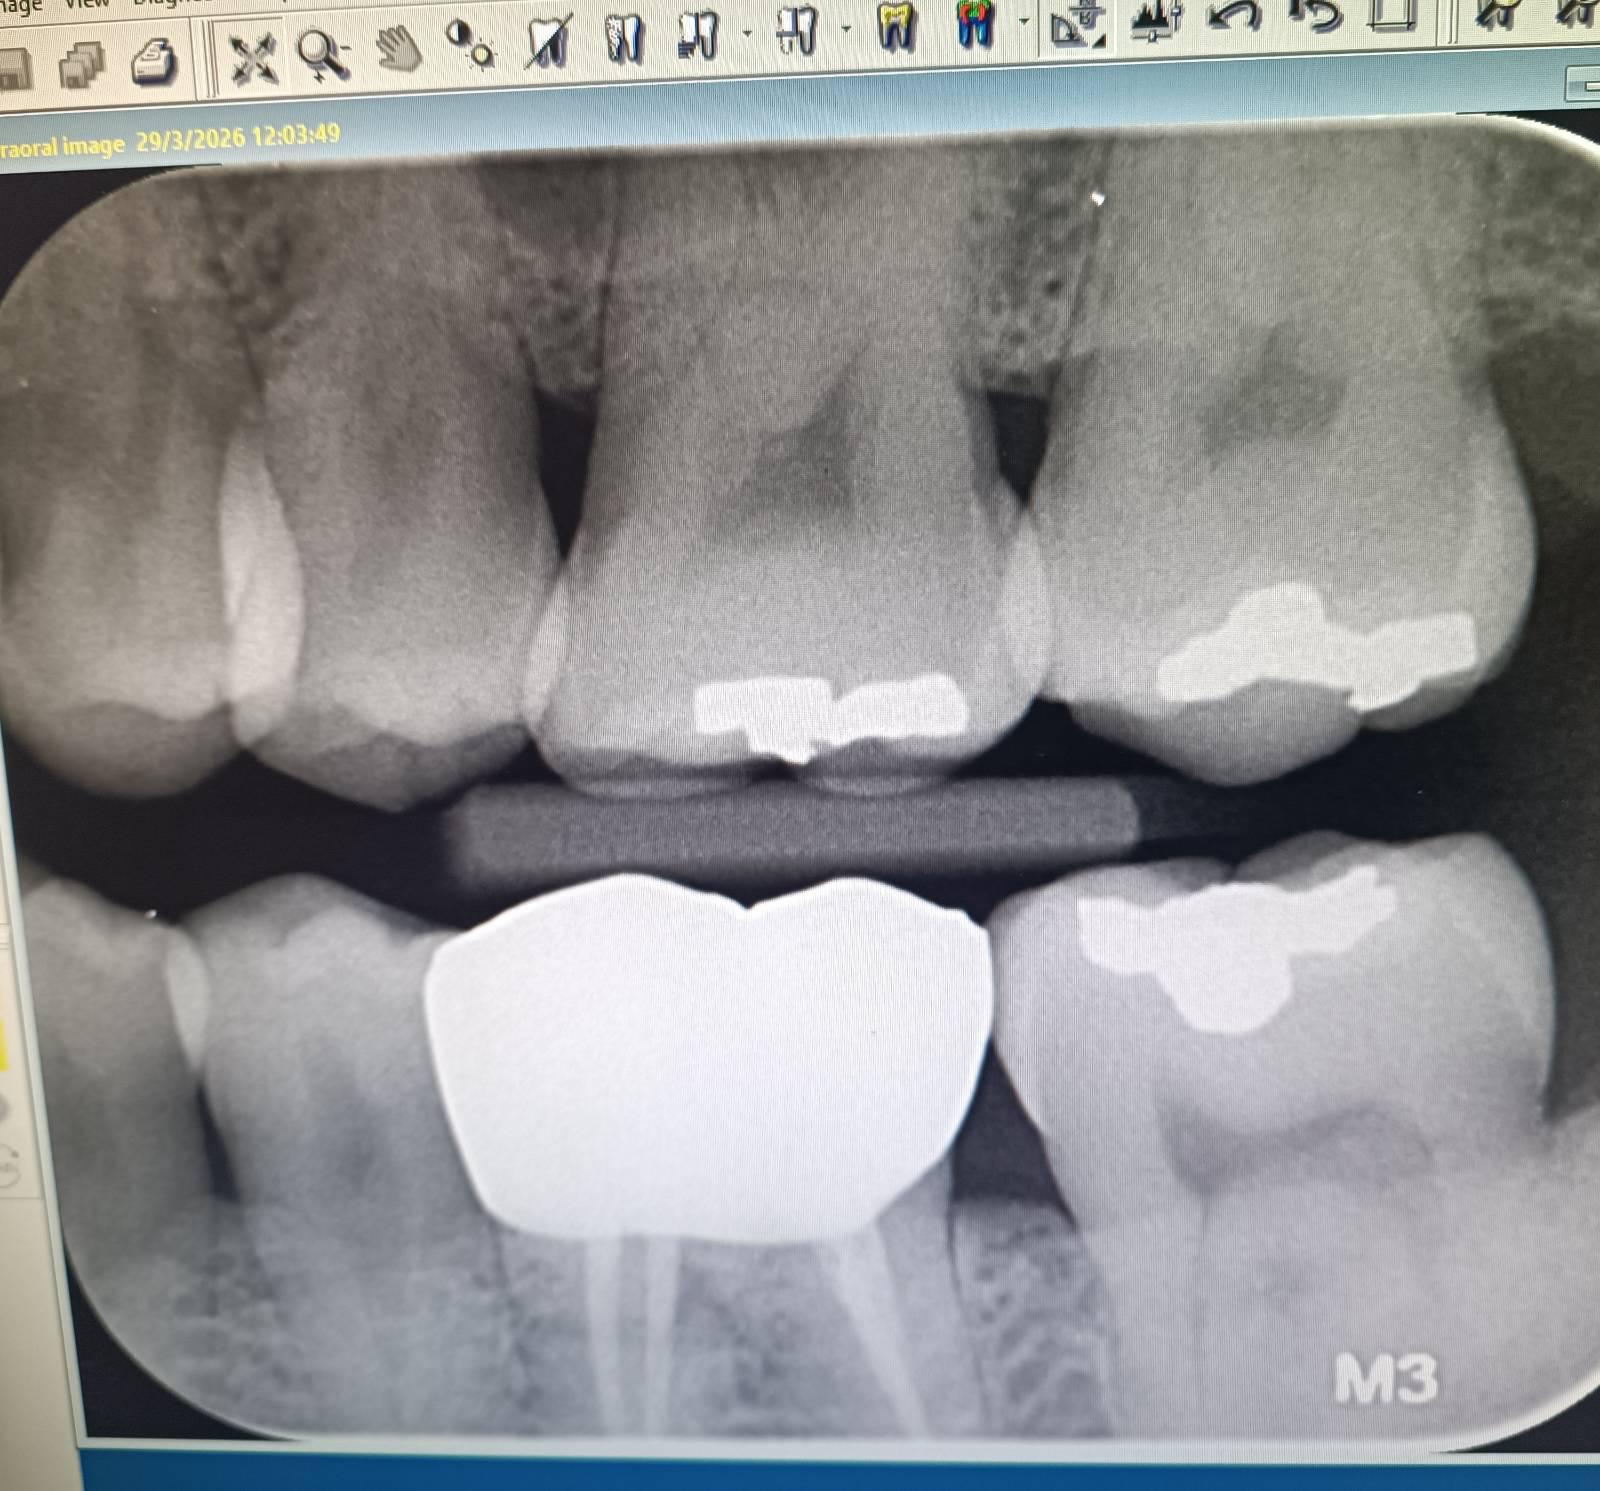

เคสนี้ ของผมเอง เริ่มจาก ไปทำครอบฟัน ล่าง มาได้เดือนนึงแล้ว ไป แต่งสบฟัน สามรอบแล้ว แต่ตอนนี้ ฟันกรามบน ที่สบกันฟันตัวครอบ เวลากินโดนของร้อน จะเจ็บขึ้นเหงือก จนระบุไม่ได้ว่า เจ็บซี่ไหน แต่ถ้าพอกัด ถึงจะรู้ว่า ซี่ไหนที่เจ็บ ก็คือ ซี่ที่ สบกับฟันที่ครอบนั่นแหล่ะ ทีนี้ พอไปเอกซเรย หมอ ก็บอกว่า ไม่มีผุ ก็ทำขูดหินปูน กับอุดคอฟัน ก็ไม่หาย หมอเค้า ก็เทสแต่ ใช้ลมเย็นเป่า แต่ก็หาไม่เจออีก พอเรา ถามว่า ผมกัดของร้อน แล้วเป็น ทำไม ไม้เทสแบบร้อน หมอบอกว่าที่นี้ ไม่มีเทสแบบร้อน หมอก็ต่อบอกว่า อาจจะเกี่ยว กับ ฟันล่าง ก็เลย เจียแต่ง ให้เตี้ยลงอีกนิด ทีนี้ มันก็ไม่หาย พอกลับมาอีกวัน พอโดนน้ำเย็น ก็เริ่มมีอาการเดียวกันละ ทีนี้ผมควรจะทำไงดี หมอก็บอกให้รอดูต่อไปอีกสองอาทิตย์ ตอนนี้ ผ่านมาอาทิตย์กว่าแล้ว ไม่ดีขึ้นเลย แต่ถ้าเคี้ยว อะไรที่อุณหภูมิปรกติ ค่อยๆเคี้ยว ก็ไม่เจ็บอะไร

แล้วอีกเรื่อง ตัวฟันที่ครอบ ผมก็บอกหมอว่า เคาะแล้ว มันจะเสียวๆ ตอนเคาะ หมอก็เอาแต่เถียง ว่าเป็นไปไม่ได้ เพราะรักษารากฟันแล้ว

แลเวจะให้พูดยังดี ก็มันมีความรู้สึกเสียวจริงๆ หมอก็ไม่ยอมเชื่อ ตอนนี้ อาการมั่วไปหมดเลย

ตรวจหาสาเหตุ ก็หาไม่เจอ ผมควรย้ายคลีนิคมั้ยครับ